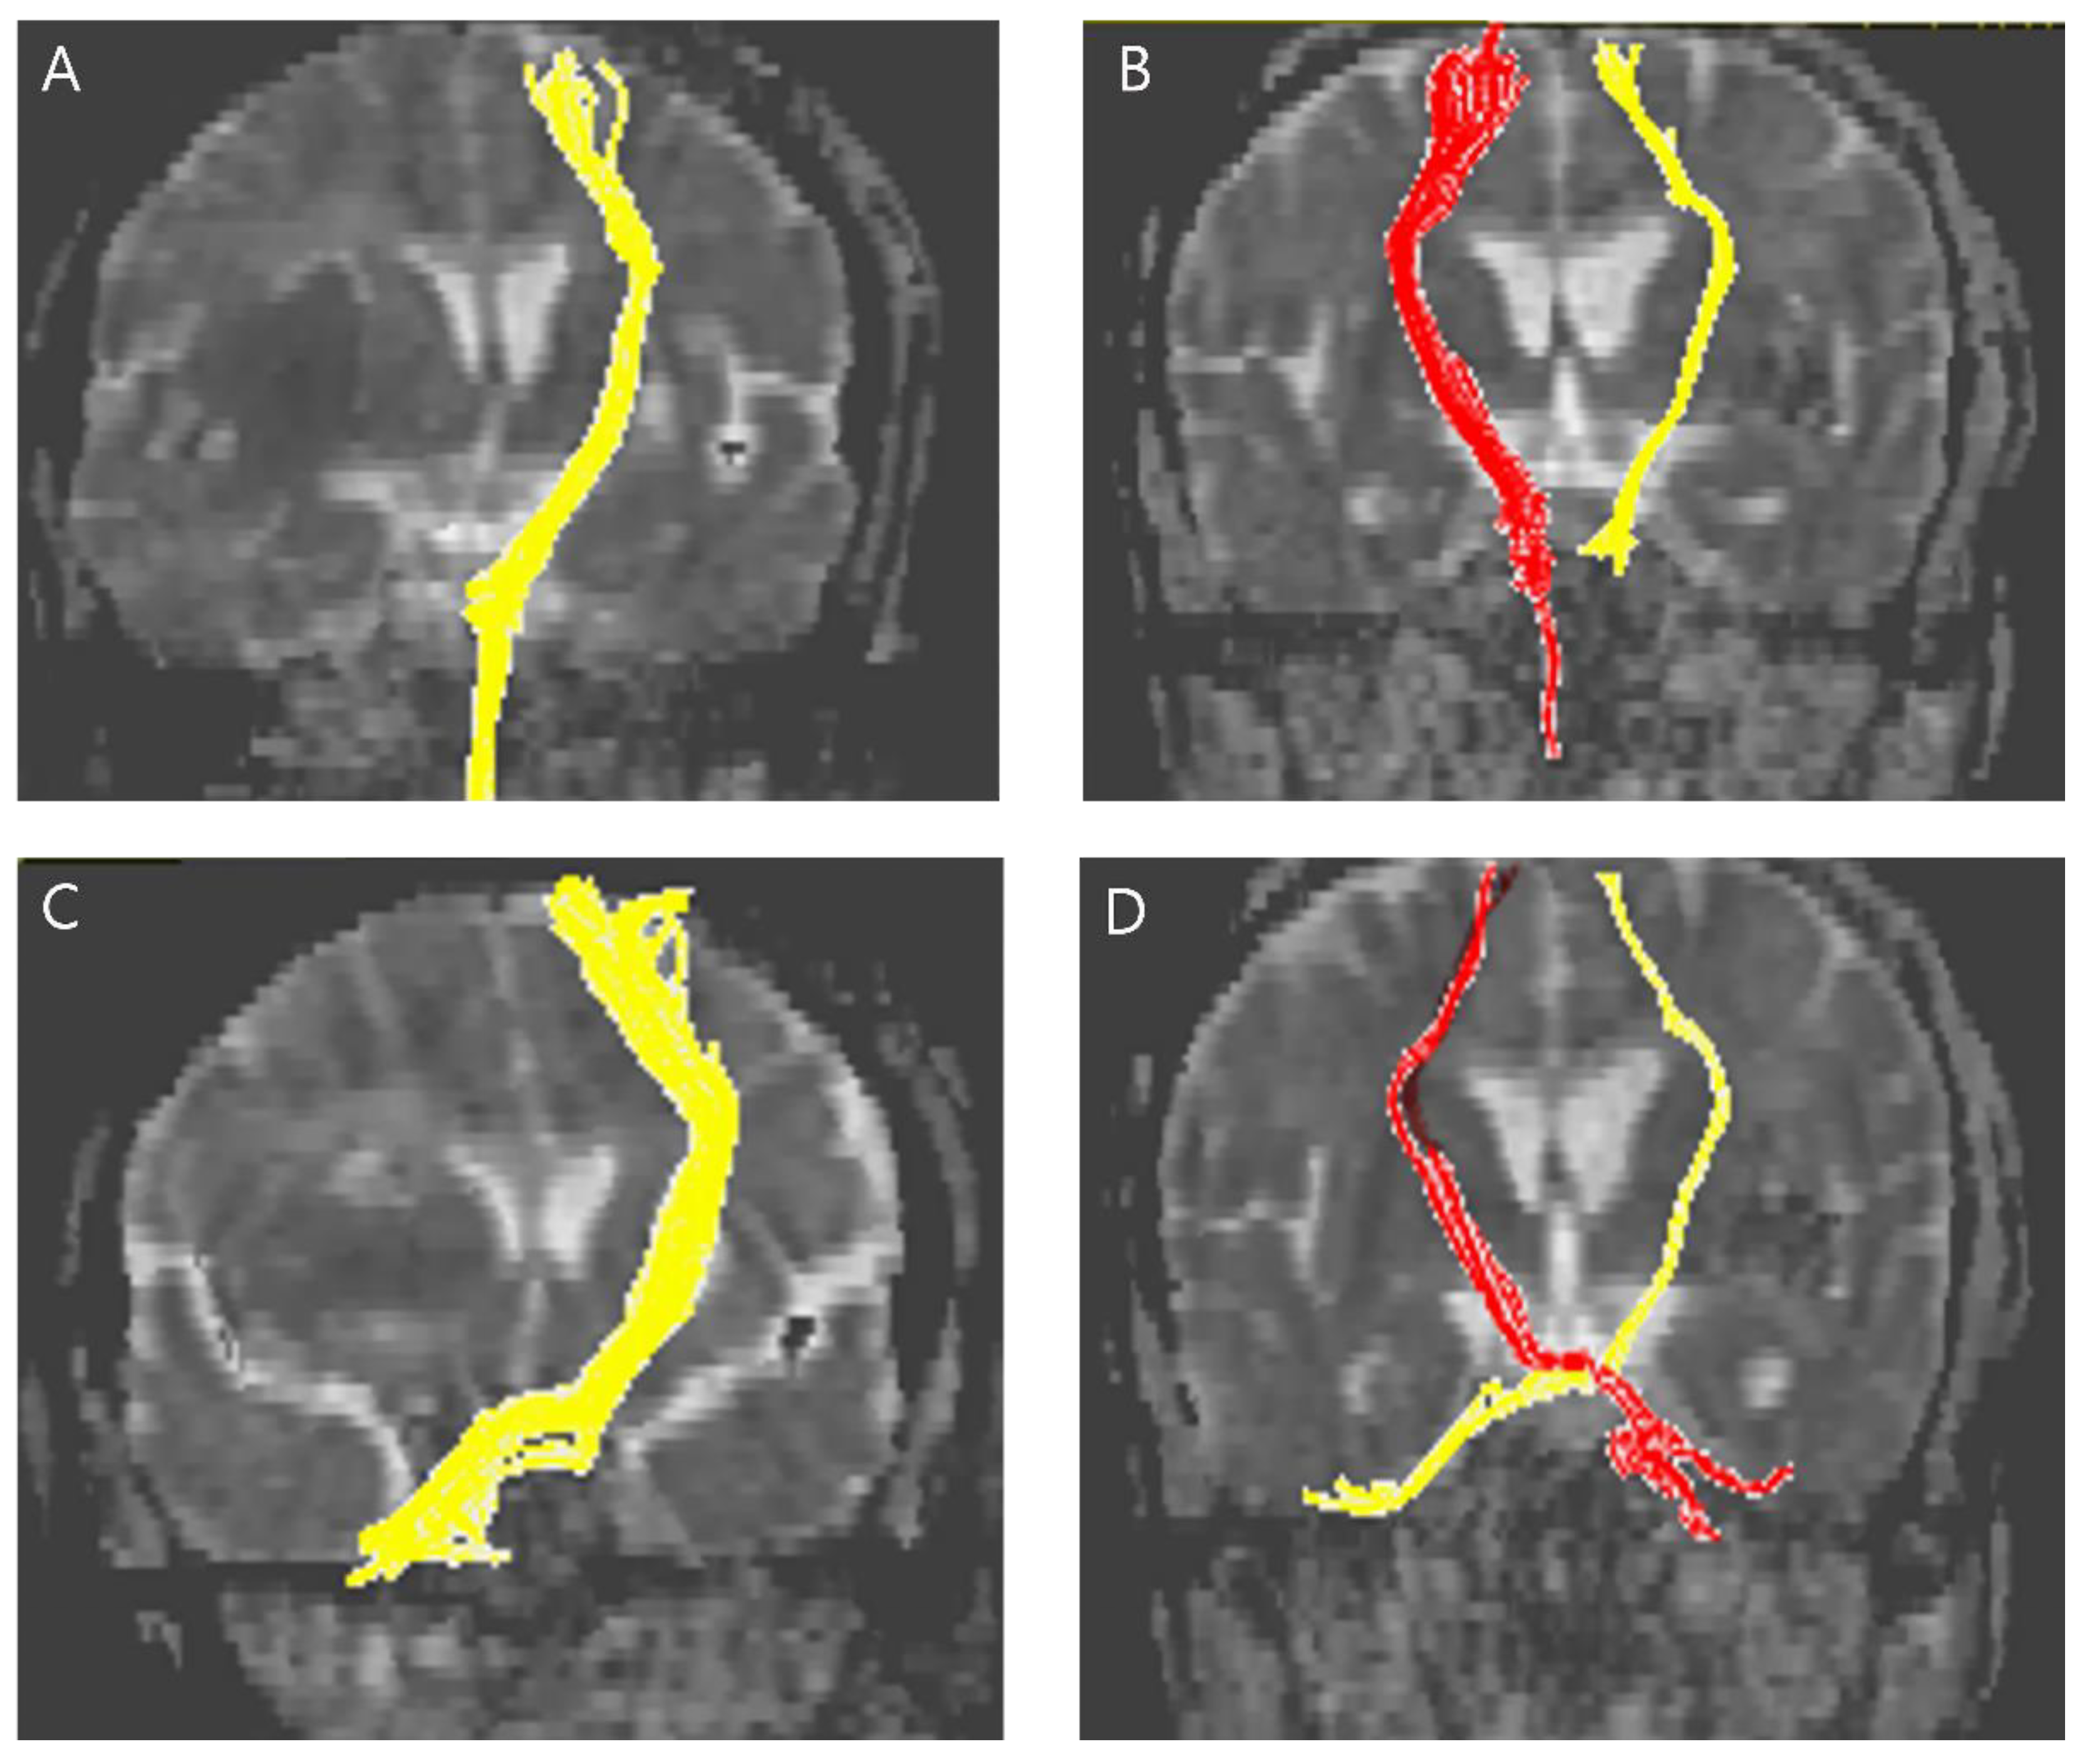

2.3. Diffusion Tensor Tractography